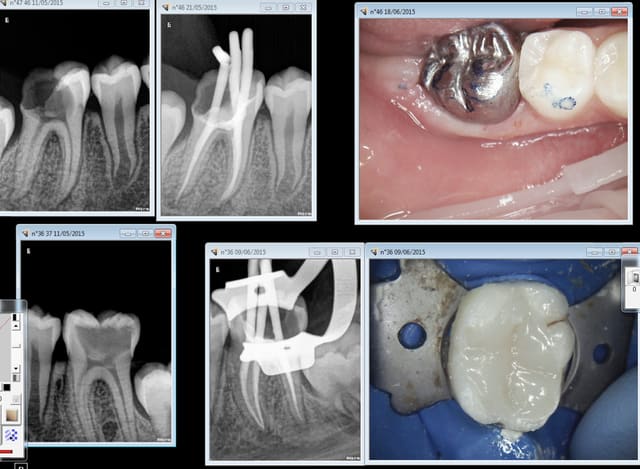

Tiens ca commence tot patiente de 9 ans CMU tout est "gratuit" ! ........ sauf la" fluoration" dans quelque temps quand les autres dent définitives seront sorties, same player shoot again . -))))

Enfoiré de chicot poser une couronne sur une patiente de 9 ans, mais toi tu commences beaucoup plus tot non ? !-)))